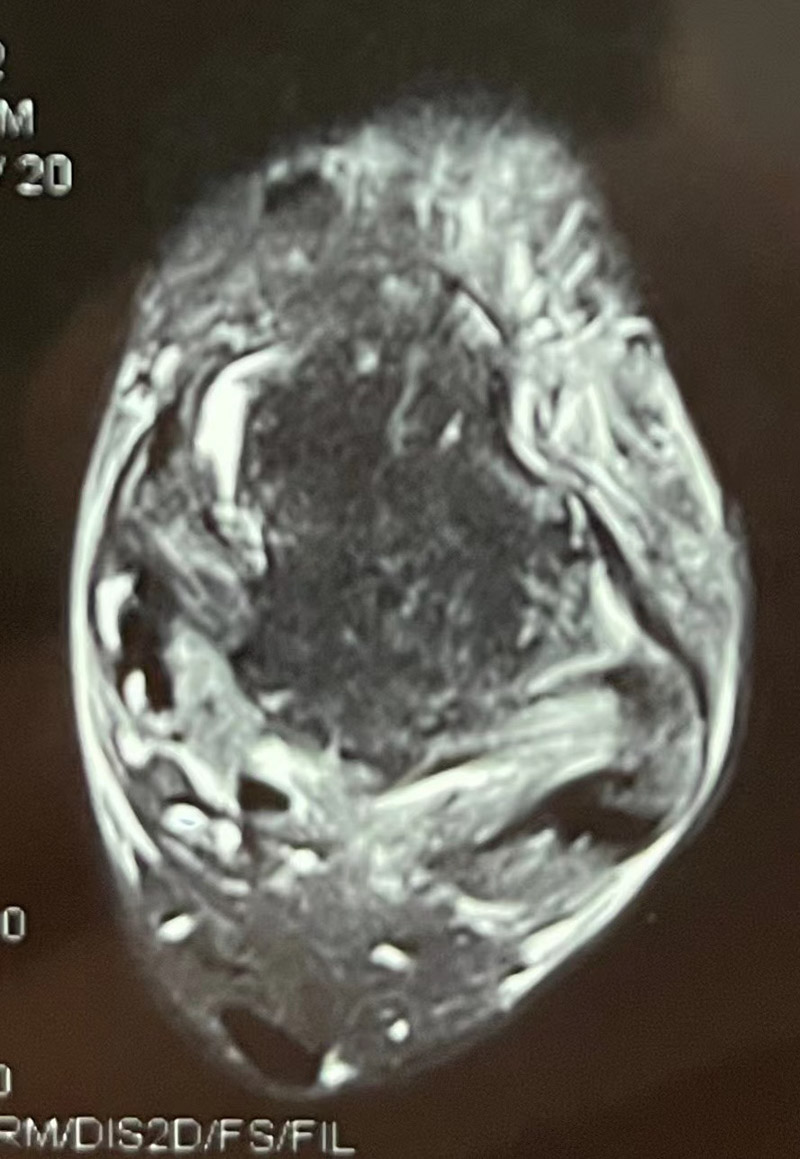

▲距腓前韌帶撕裂

“大家總是認為,踝關節扭傷,休息休息就好,其實,有可能是踝關節距腓前韌帶撕裂所致的關節失穩。”韋釗嵐說,“踝關節扭傷在關節及韌帶損傷中是發病率最高的疾病,占所有運動損傷的40%左右,而踝關節的穩定性對于日常的活動和體育運動的正常進行起重要作用,是絕對不可小覷的。如果腳踝第一次扭傷時未得到及時診治,容易引起經常性的反復扭傷。扭傷不僅造成軟骨的撞擊,包括增生的疤痕組織等,也會造成關節的撞擊,產生撞擊綜合征,造成關節反復的腫痛與不適。”